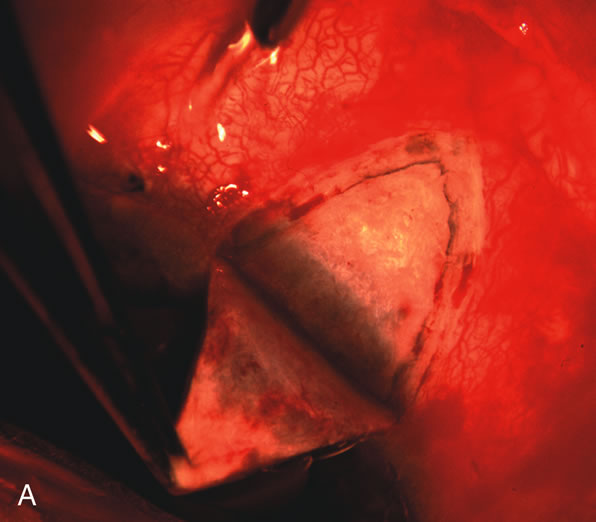

Cataract extraction by any technique performed in a patient with a pre-existing filter will have an effect on the previous filtering bleb.121–124 Bleb failure is more likely with ECCE compared with small-incision phacoemulsification.125 However, even patients undergoing topical anesthesia with clear corneal phacoemulsification and foldable IOL may experience bleb failure. One of three patients with a functioning filter and preoperative mean IOP of 12 mm Hg without antiglaucoma medications experiences bleb failure after lens extraction (Table 2). These patients require long-term drug therapy or bleb needling to control IOP. 126 Additional incisional glaucoma surgery may eventually be required in up to 10% of patients.127 Intraoperative iris manipulation may cause significant breakdown of the blood–aqueous barrier, resulting in inflammation that causes bleb failure. Even after uncomplicated clear corneal phacoemulsification, IOP may increase an average of 2 to 3 mm Hg due to bleb fibrosis.128 Approximately 20% of filtered patients require a long-term increase in glaucoma medications following uncomplicated clear corneal phacoemulsification with a foldable copolymer acrylic IOL129 (Fig. 3). In situations in which the bleb is not working at all, the eye will have a postoperative pressure spike that mimics that in the patient not having had a prior filtering procedure. In situations in which the bleb is marginal, the pressure spikes tend to be lower, and the final postoperative IOP tends to be around 50% higher than it was preoperatively. These patients require combined procedures in order to reestablish long-term filtration. In situations in which the bleb is very thin, polycystic, and associated with an IOP around 5 to 8 mm Hg on no antiglaucoma therapy; uncomplicated cataract extraction will have a minimal effect on the level of IOP. Patients with functioning glaucoma drainage implants usually have minimal long-term changes in IOP after uncomplicated cataract extraction.130

Fig. 3. Partial bleb failure following clear corneal phacoemulsification with foldable IOL. A. Preoperative bleb appearance prior to temporal lens extraction. Preoperative IOP was 12 mm Hg on no antiglaucoma medications. Time from 5-FU trabeculectomy surgery to lens extraction was one year. B. Bleb appearance 2 months after clear corneal cataract surgery with topical anesthesia. Following lens extraction, increased vascularity was noted along with decreased size of the filtering bleb. IOP increased to 20 mm Hg as early as 2 weeks after surgery, necessitating topical antiglaucoma therapy. C. High magnification view of bleb before lens extraction demonstrates diffuse pale bleb. D. High magnification view of bleb 2 months after surgery. There are vessels surrounding the nasal side of the bleb and the overall bleb size is smaller.